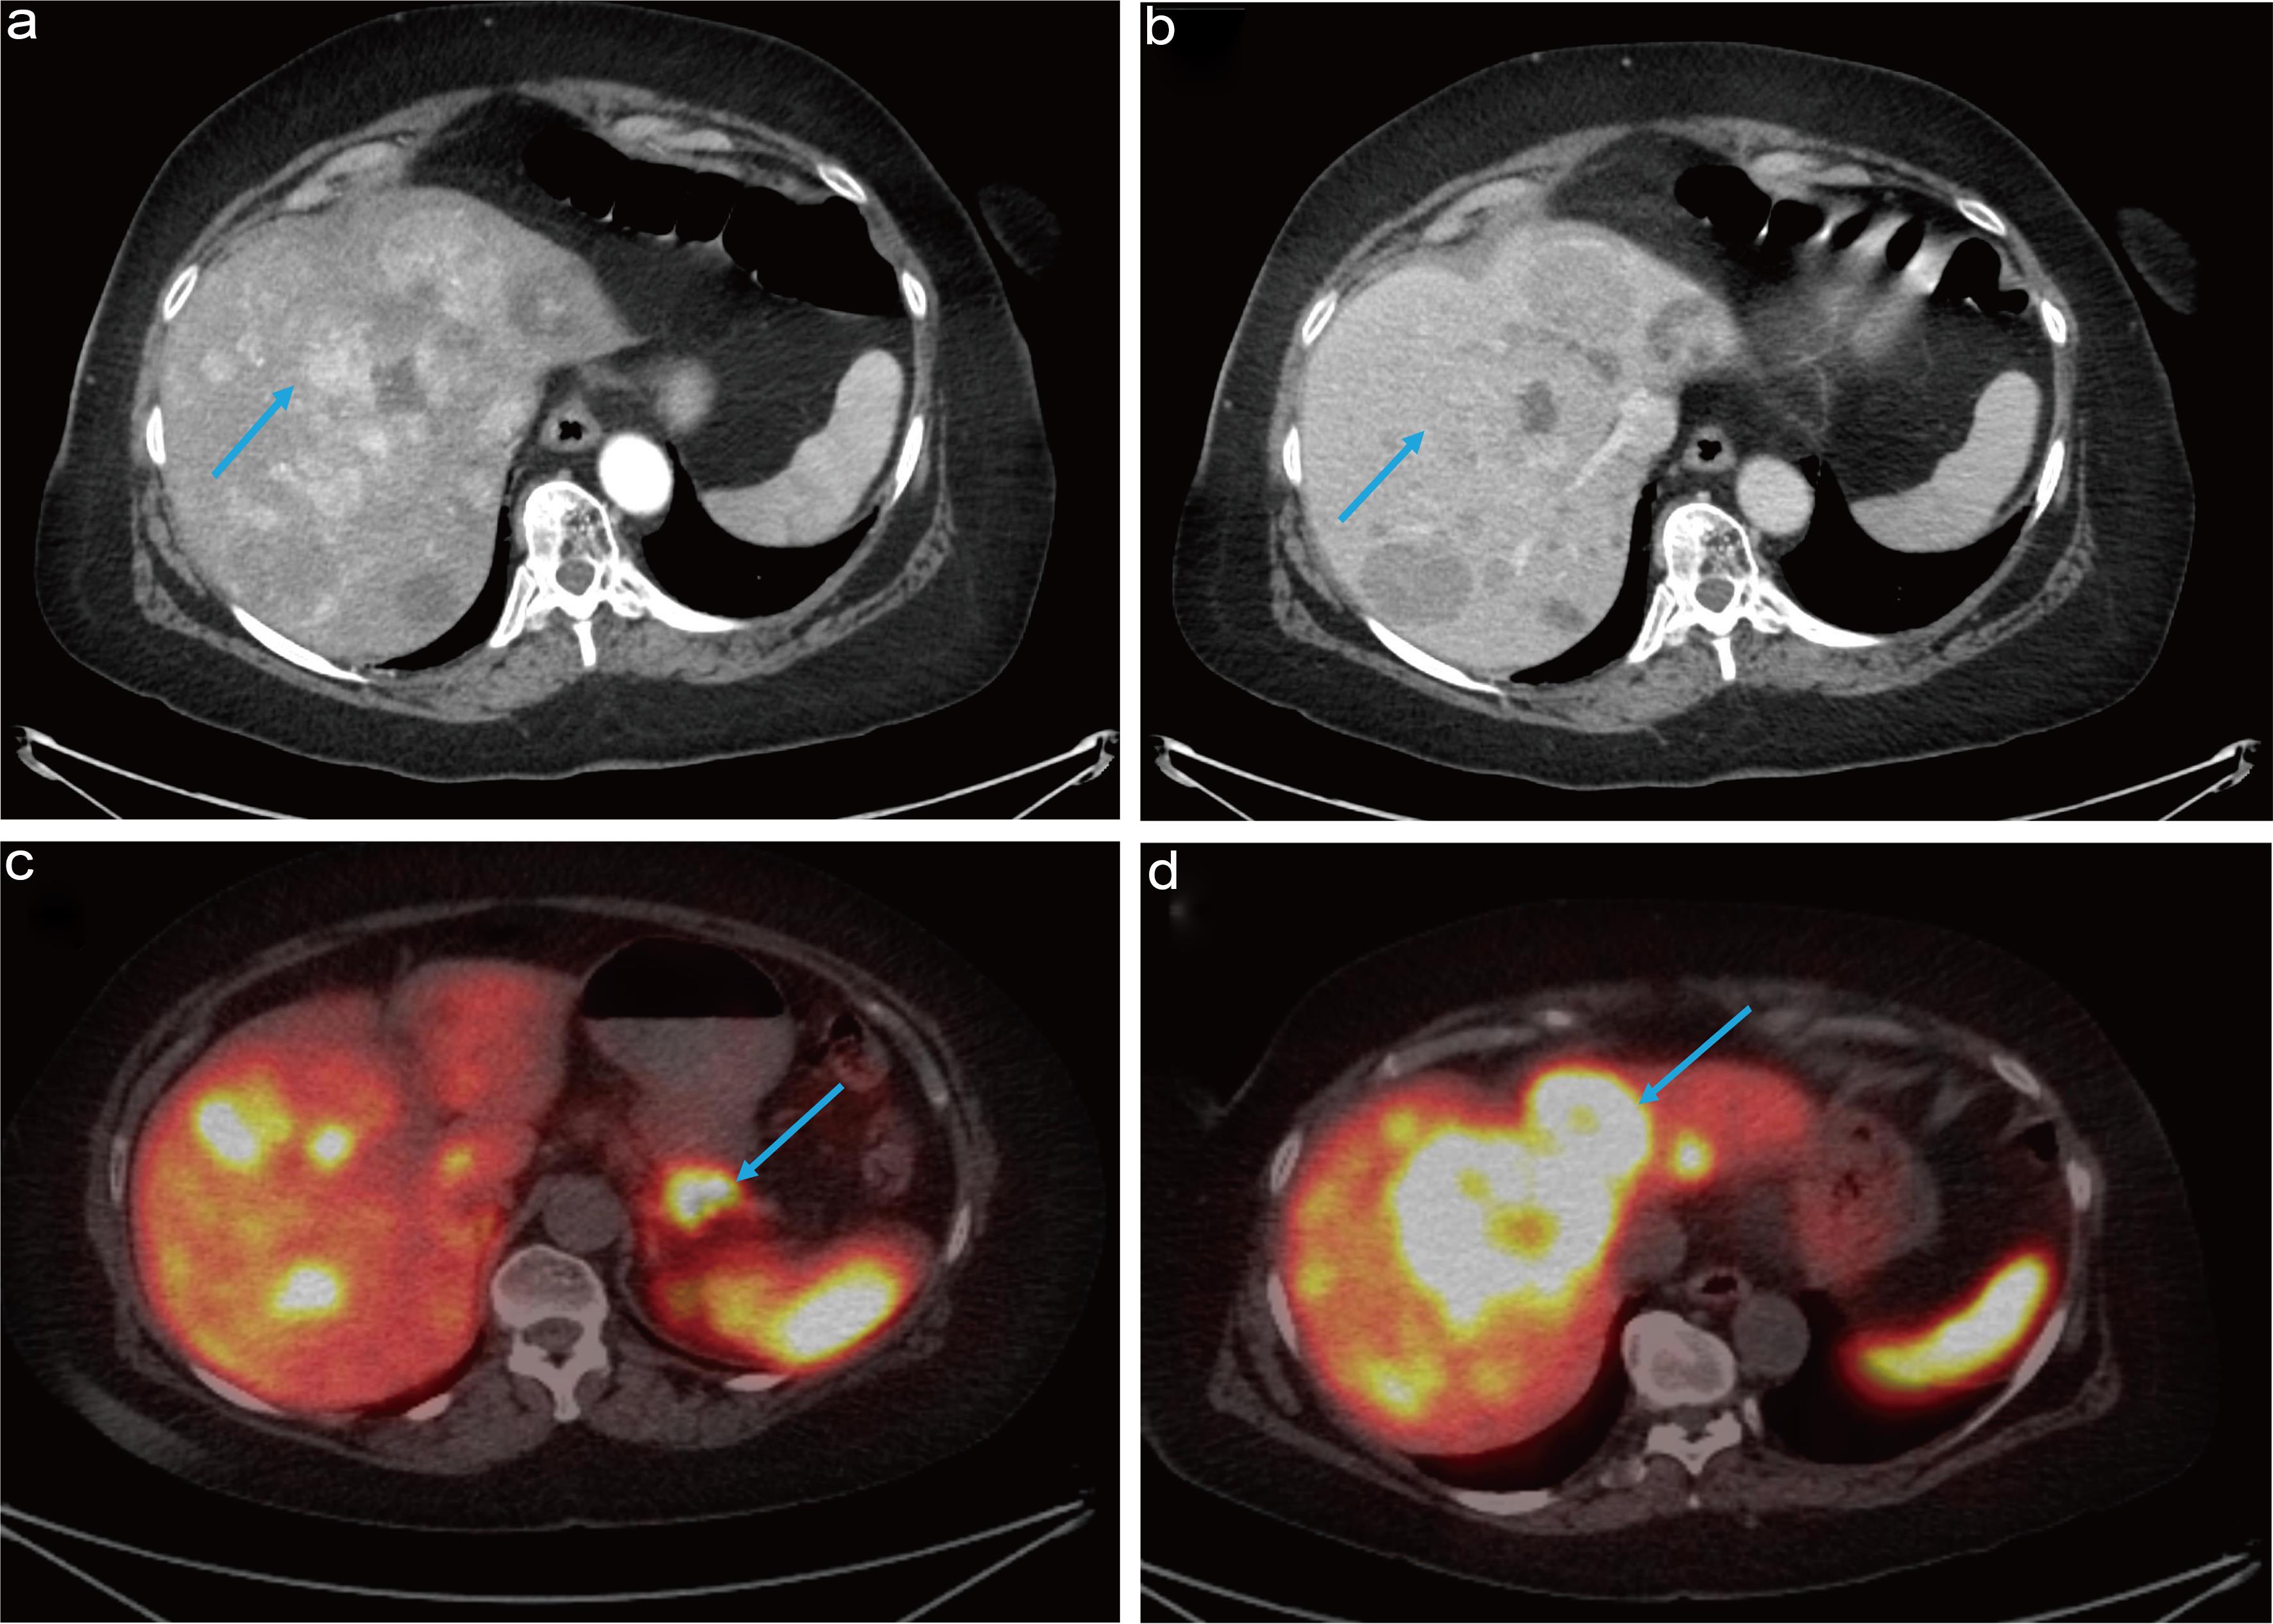

Clinical Response to Sequential HAIC and TAE Combined with Tislelizumab and Lenvatinib Treatment for Hepatocellular Carcinoma Involving Lung Metastases: A Case Report

Jian-Rong Li, Da-Long Yang, Jia-Yong Su, Cai-Yi Dong, Wen-Yang Li, Xiu-Qiong Long, Xiao-Shan Qin, Bin-Yan Gu, Liang Ma, Jian-Hong Zhong

Published online: May 28, 2025

[ Html ] [ PDF ] [ Google Scholar ] [ Cite ]

doi:10.14218/JTG.2025.00008